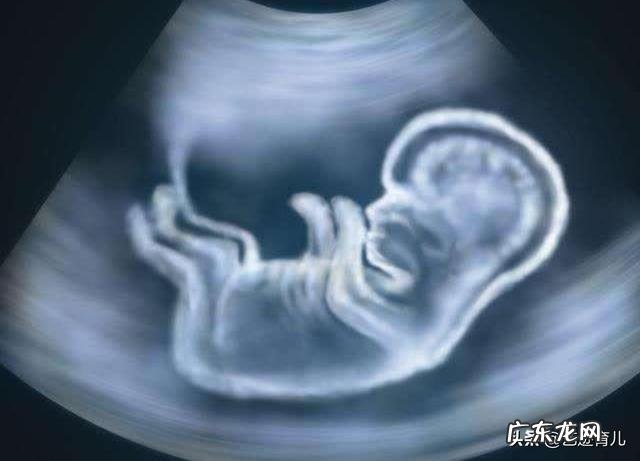

胎儿股骨长决定身高吗为什么股骨长是胎儿的大腿骨的长度,同时它也是在孕期里面,胎儿最大的长骨头,但它是不是一直决定胎儿出生以后的身高呢!很多的孕妈每次看到股骨长度,就立马跑去找医生,“医生我家宝宝股骨长是不是太短了,长大以后会不会得侏儒症呀”!

孕期里面有测量胎儿股骨长,很多孕妈就觉得这是影响胎儿身高最大的因素,准确的说,在孕期里面,胎儿的股骨长多少都会影响到胎儿的长度,但是胎儿在孕妈肚子里的体位也会直接影响到胎儿的股骨长度,而且医生在测量的时候,手法和胎儿的活动,都会给胎儿的测量准度有一定的影响,所以也会有很大的误差 。

医生在孕期里面检查胎儿股骨长、双顶径、孕妈腹围、身高,其实这些数据都是为了推测胎儿发育情况,如果这些数据有异常,那么就说明胎儿可能发育有一定的问题,比如说孕妈腹围增长速度,如果在20周的增长速度小0.85cm那么可能存在胎儿发育缓慢导致,还有胎儿有缺氧的情况,所以医生也是从一些数据推测出胎儿可能存在的问题 。